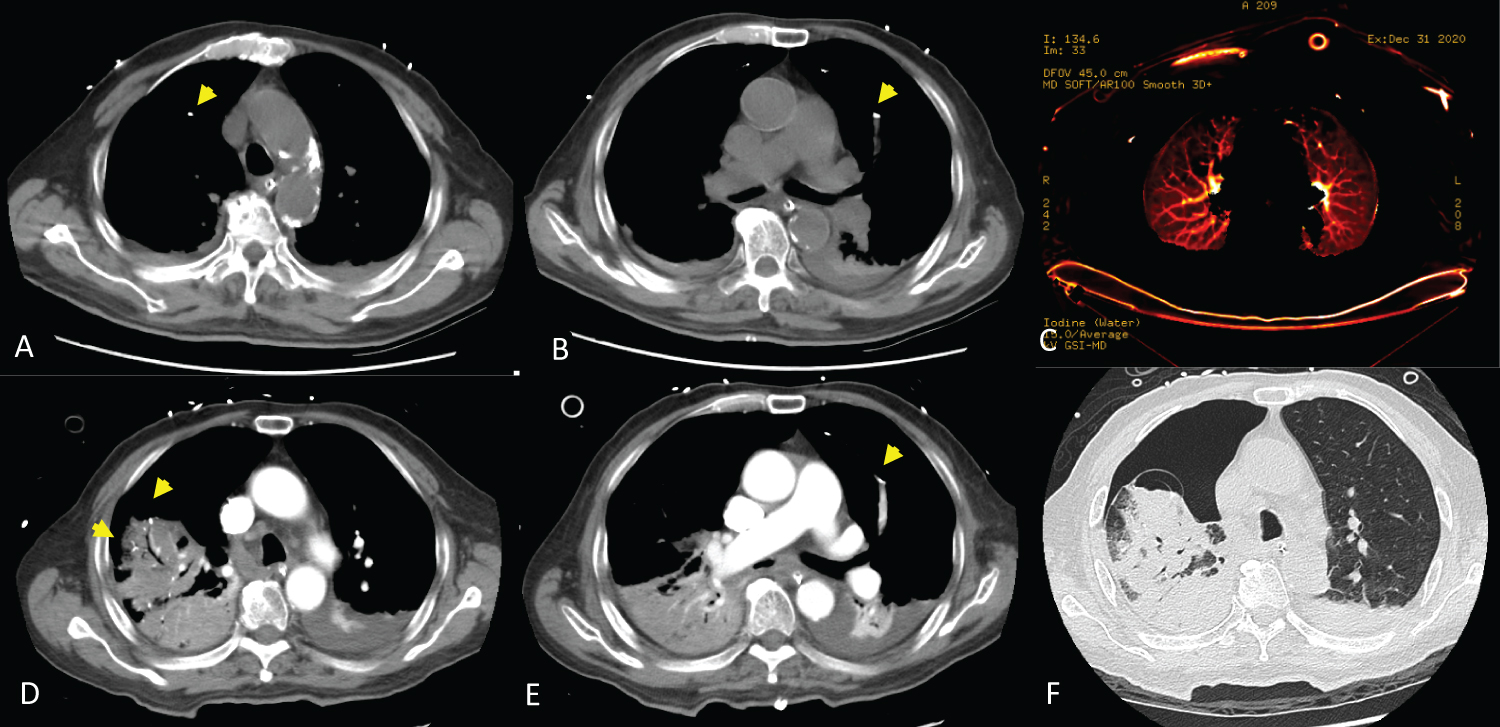

On the third postoperative day, the patient developed a mild productive cough with yellowish sputum, and chest plane film showed pronounced lung markings. Chest CT revealed subsegmental cement embolism at the bilateral upper lung field with reduced perfusion (Figure 3A, Figure 3B and Figure 3C). Owing to a fair respiratory condition and lack of other symptoms except a productive cough, no anticoagulant agent was prescribed. Extubation was done smoothly. After two more days of close observation and monitoring in the ICU, the patient was transferred to the ordinary ward on the fifth postoperative day.

Figure 3: Postoperative chest computed tomography.

Chest computed tomography on the third postoperative day showed scattered small tubular and branching dense opacities (arrow) along the course of the subsegmental arteries over bilateral anterior upper lung fields, with pulmonary cement emboli (A,B); Reduced perfusion was noted over those regions (C); Chest computed tomography on the fifth postoperative day revealed many visible cement emboli (D,E); Right lung atelectasis, bulla formation over the right upper lung adjacent to the cement embolus, and right-sided pneumothorax (F). View Figure 3

Endotracheal intubation was performed for respiratory failure, and he was transferred to the ICU. Chest CT was repeated and revealed right lung atelectasis, bulla formation over right upper lung adjacent to the cement embolus, and right-sided pneumothorax (Figure 3D, Figure 3E and Figure 3F). The bulla formation, which might be related to a pulmonary infarction and resulted in pneumothorax, was not seen on previous CT series. A chest tube was inserted into the right pleural cavity for drainage. Due to pneumothorax with persistent air leakage, the setting of the mechanical ventilator was conservative. The inspired oxygen fraction could barely taper. Arterial PO2 (PaO2) on an FiO2 of 0.8 was 86.1 mmHg. The ratio of PaO2 to inspired oxygen fraction (P/F ratio) was 107.6, which confirmed ARDS. Delayed presentation of severe symptomatic PCE was observed. Laboratory profile revealed elevated D-dimer 3.77 mg/L (normal range: less than 0.56) and C-reactive protein 12.33 mg/dL. Other laboratory parameters were within the normal range. Antibiotics were prescribed for coverage of any possible infection.